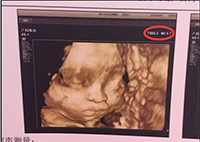

從四維單子mi和fmi的區(qū)別預(yù)測懷孕生男生女,居然還有網(wǎng)友說真的超準(zhǔn),真不知道這些答案是從哪里道聽途說來著的。懷孕期間想預(yù)測男女的朋友,請你別打四維單子上M與F暗示胎兒性別...

現(xiàn)在有許多媽媽說通過四維彩超可以查看男女,說是四維彩超里男女寶寶圖片是有區(qū)別的,為了證實(shí)這一切的真假性,下面,趕緊隨本文一起來看看,四維男女寶寶區(qū)別圖有何不同,及如何利用...

有人說四維彩超單上的F和M字母代表胎兒性別,m開頭是男孩f是女孩對,難道四維單子有暗示男女嗎?如果真的如傳言所說,那么問題又來了,四維單子上怎么看m和f呢?...